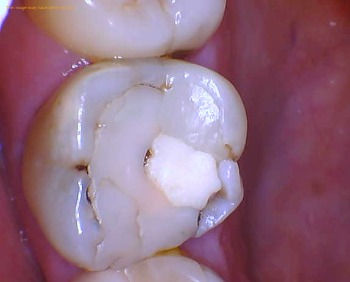

Procedure Step by Step with Photos

A dental filling is a restorative procedure that removes tooth decay and replaces it with a restoration. Oral bacteria can cause cavities on any surface of your tooth but you can fix it with a dental filling in Long Island City.

The obvious symptoms of a cavity is sensitivity to sweets or pain when eating. However, just because you're not experiencing a toothache, it doesn't preclude you from needing dental treatment.